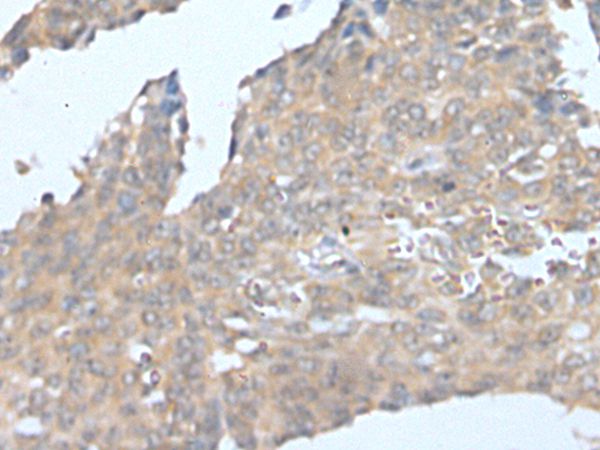

The image on the left is immunohistochemistry of paraffin-embedded Human ovarian cancer tissue using CSF1 Antibody at dilution 1/25, on the right is treated with synthetic peptide. (Original magnification: x200)